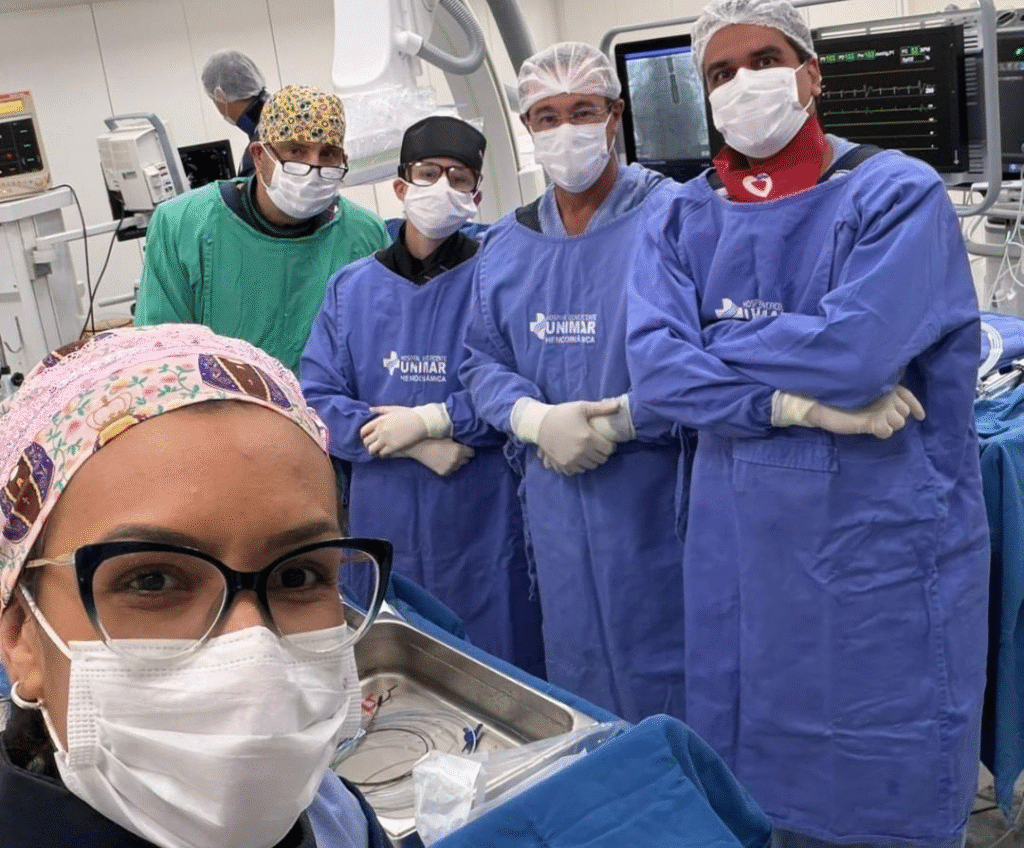

O procedimento contou com a atuação de um “Heart Team”, uma equipe multidisciplinar essencial para intervenções cardíacas dessa complexidade, reunindo profissionais de diferentes especialidades.

Integraram a equipe os cardiologistas intervencionistas, Ricardo José Tofano e Marielle Rodrigues Martins, os cirurgiões cardíacos Sideral Ferreira Alves e Diego Gaia, o ecocardiografista Marcelo Peron e o anestesista José Luiz.

“Nenhum procedimento como esse é feito de forma isolada. Ele depende de um Heart Team completo, experiente e bem alinhado. Cada profissional tem um papel fundamental, desde a avaliação inicial até o acompanhamento pós-procedimento. Esse trabalho em equipe é o que garante segurança e excelência ao paciente”, finaliza.